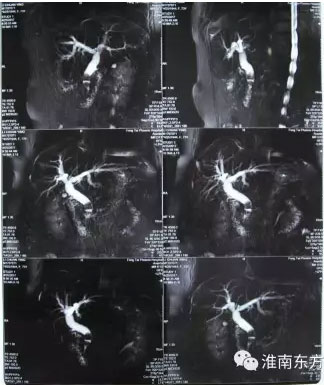

凤台县刘集乡75岁女患者李某,十年前因胆囊结石曾做过胆囊切除手术。十年后,李某再次因腹痛发热住进了我市市区一所大医院,诊断为胆总管多发结石,最大结石直径已经接近1.5cm。因该院不具有ERCP技术,只能建议李某再次实施传统的开刀手术取石。由于李某年事已高,且十年前已经做过胆囊切除手术,再次手术不仅风险大,成功率也会相对降低。家属通过多方打听后,决定将李某转入我市ERCP技术最棒的东方医院继续治疗。

经过精心的术前各项准备工作,上午9点,手术按预定时间正式开始,张军主任在台上实施,江永强院长亲自在监视器前指挥作战。仅仅20多分钟后,患者胆总管结石被顺利地全部取出,手术完美收官。